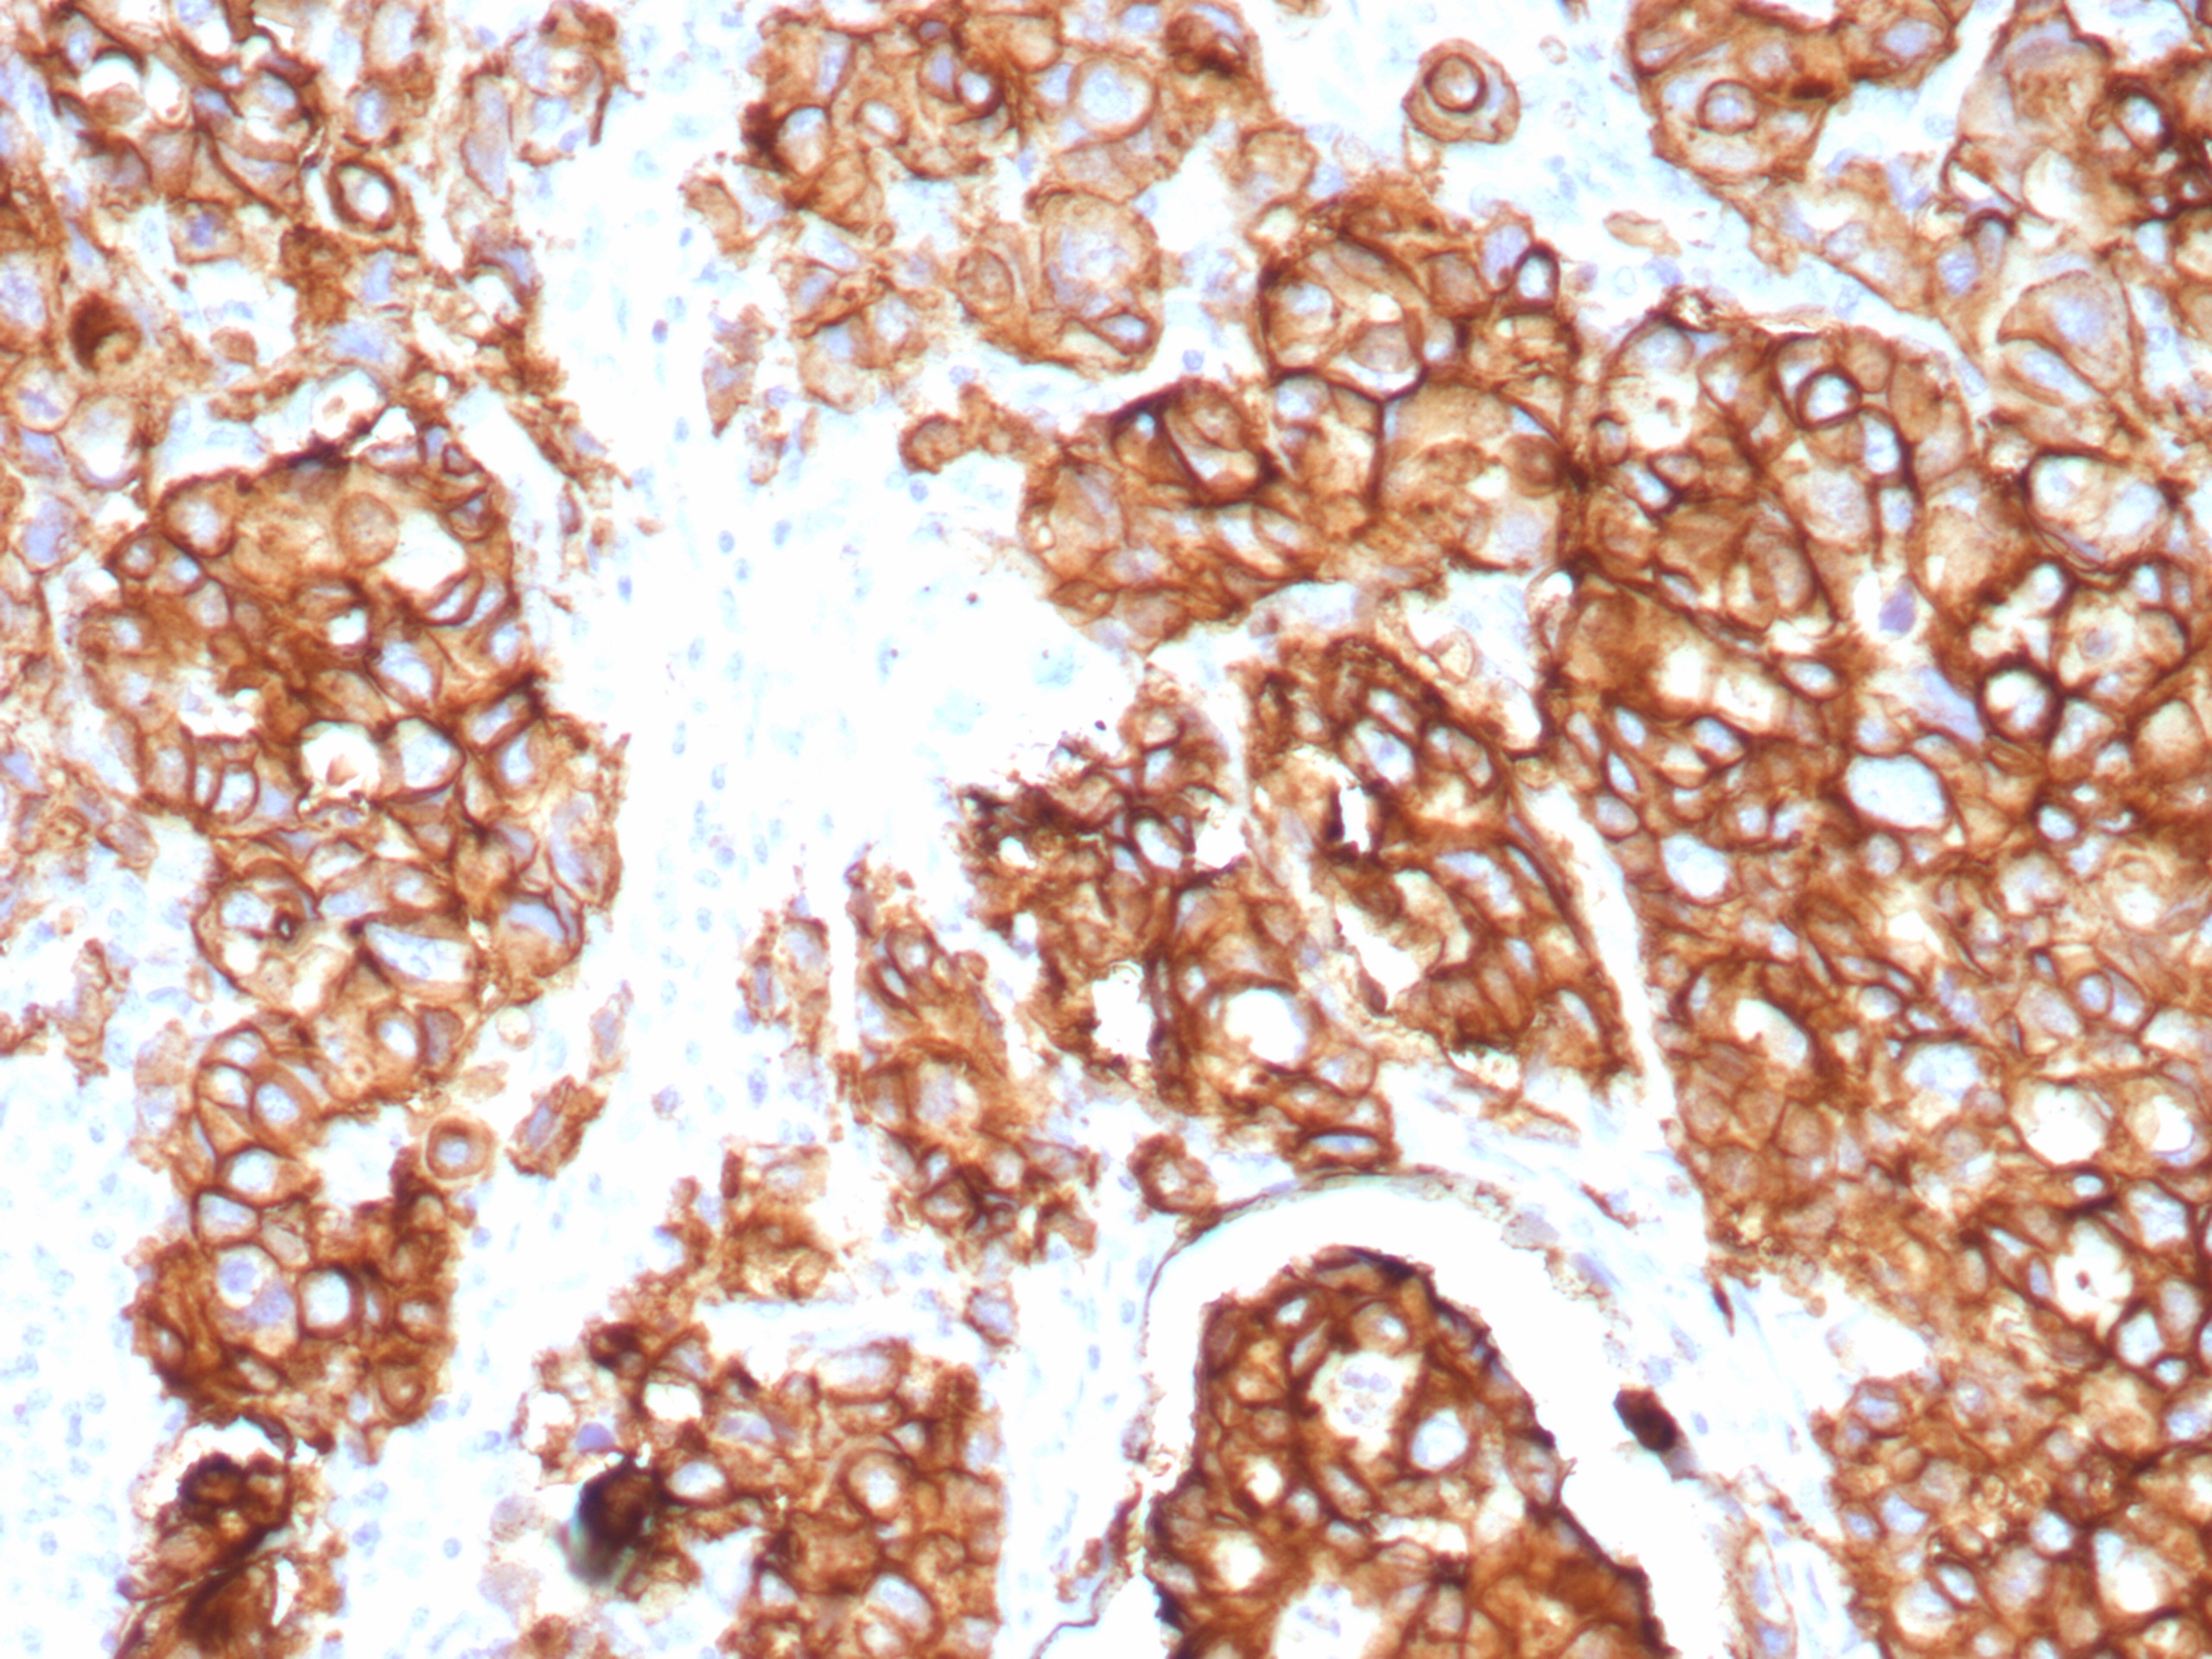

Formalin-fixed, paraffin-embedded human colon carcinoma stained with EpCAM Recombinant Rabbit Monoclonal Antibody (EGP40/8774R). Inset: PBS instead of primary antibody; secondary only negative control. HIER: Tris/EDTA, pH9.0, 45min. 2°: HRP-polymer, 30min. DAB, 5min.

Binding epitope of this antibody is located in the first EGF-like repeat domain (EGF1) between amino acids 27-59 of Ep-CAM.EGP40 is a 40-43kDa transmembrane epithelial glycoprotein, also identified as epithelial specific antigen (ESA), or epithelial cellular adhesion molecule (Ep-CAM). It is expressed on baso-lateral cell surface in most simple epithelia and a vast majority of carcinomas with the exception of adult squamous epithelium, hepatocytes and gastric epithelial cells. This antibody has been used to distinguish adenocarcinoma from pleural mesothelioma and hepatocellular carcinoma. This antibody is also useful in distinguishing serous carcinomas of the ovary from mesothelioma.